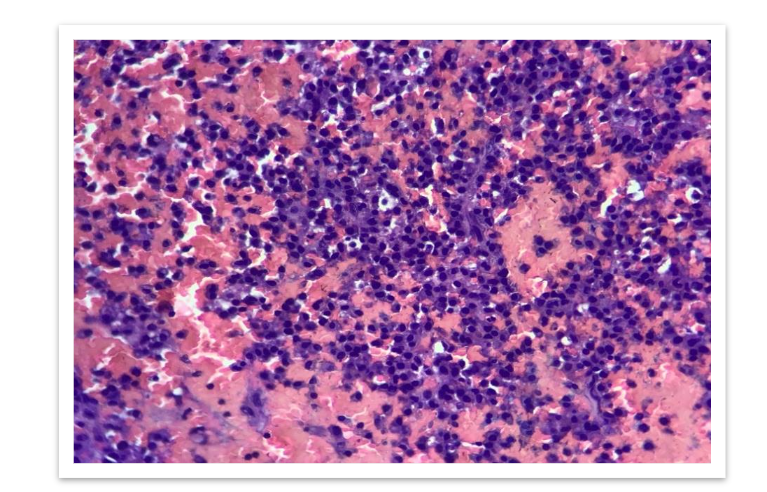

Microscopically, loosely arranged clusters of plasmacytoid cells, some are seen embedded in an eosinophilic osteoid like stroma. Few areas showed neutrophilic infiltration, spicules of degenerated bone, areas of haemorrhage and few bundles of striated muscle fibres. It was reported as Plasma cell malignancy- probably multiple myeloma (Non secretory type) as serum protein electrophoresis was normal.

Bone marrow biopsy was performed, which showed a hypercellular marrow with increased plasma cells constituting more than 20% of total leukocytes. The plasma cells were positive for CD138, confirming the diagnosis of non-secretory multiple myeloma.